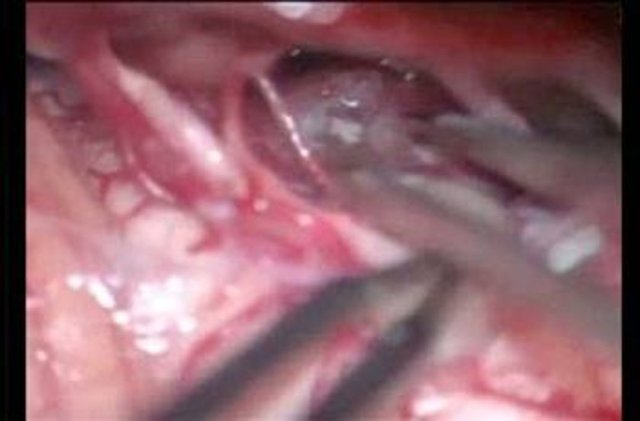

Kahramanmaraş'ın Afşin ilçesinde bir genç kız, karın ağrısı şikayetiyle gittiği hastanede, midesinde çatal olduğunu öğrenince şok oldu. Genç kızın çatalı küçük yaşta yuttuğu sanılırken, çatal başarılı bir ameliyatla çıkarıldı.